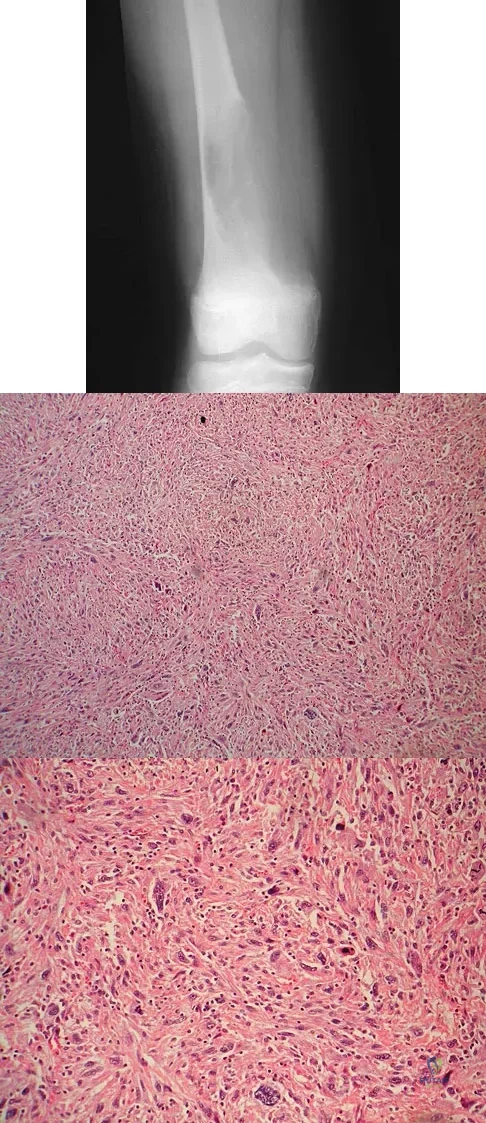

An 18-year-old boy has had pain in the right knee for the past 6 months. Examination reveals some fullness behind the knee but no significant palpable soft-tissue mass. There is no effusion, and he has full knee range of motion. The remainder of the examination is unremarkable. A radiograph and MRI scans are shown in Figures 33a through 33c, and biopsy specimens are shown in Figures 33d and 33e. What is the most likely diagnosis?

Explanation